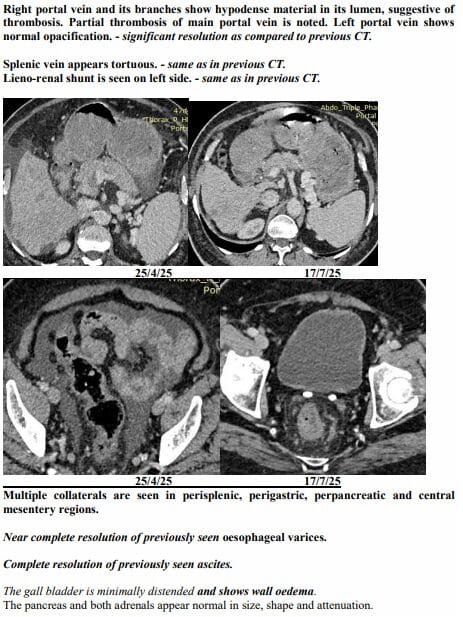

Yet just three months later, on another afternoon in July, the same family stared at a different scan. The tumours had shrunk to one patch. Blood was flowing again. The swelling was gone. Even the alarming tumour marker that had shot up to 1,000 ng/mL had fallen to 10, back in the safe zone. For a man who had been fading fast, it was a turnaround no one in the room dared to predict.

Ravjibhai’s case became proof of concept. Prescribed a personalised herbal regimen meant to reduce tumour load, restore liver function and boost immunity, he began showing slight changes in weeks. The fever broke. Jaundice eased. He ate a little more each day and walked a little further. His family noticed he was laughing again, something they hadn’t heard in months.

The July scan sealed what they were already feeling at home. The many shadows in his liver had shrunk into one. His abdomen, once swollen with fluid, was flat again. His numbers, which had scared even seasoned oncologists, were suddenly within range.